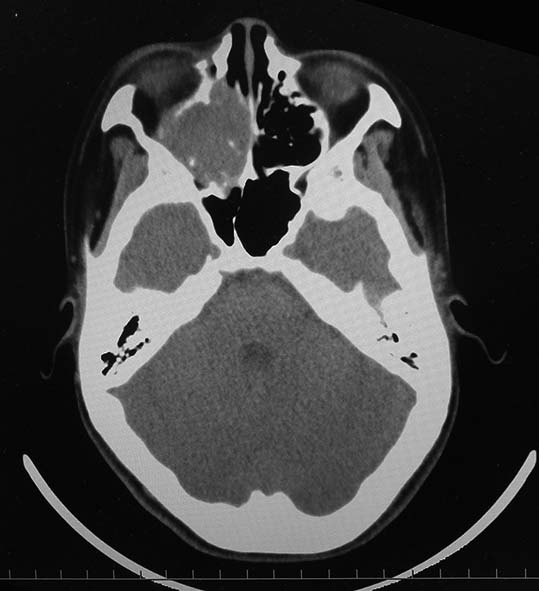

CT所見

副鼻腔腫瘤生検組織

日本病理学会中部支部交見会のスライドより。(S.Suzuki Dr.)